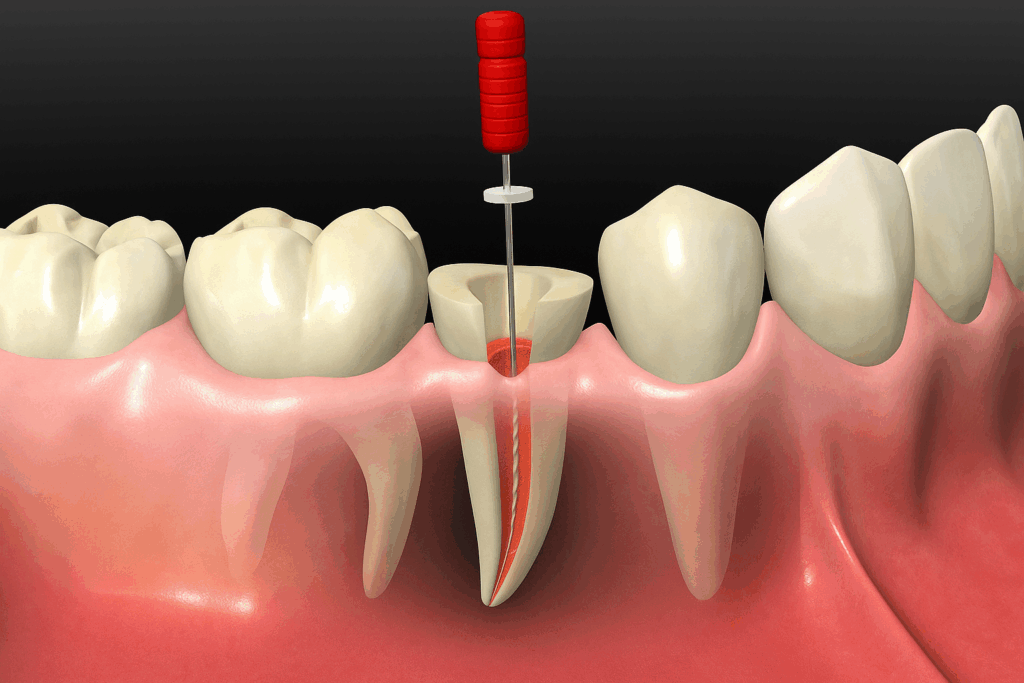

그 방법으로는 상악동 거상술이라 하여

얇아진 치조골의 상부를 들어 올린 후

그 공간에 이식재를 보강하는 방식으로

임플란트가 자리 잡을 수 있는

공간을 확보하는 것입니다.

이 방식은 치조정 접근법과

측방 접근법으로 나뉘게 되는데,

지금처럼 치조골이 흡수가 심한 경우

측방 접근법을 시행합니다.

치조골의 옆쪽,

즉 측면에 작은 창을 내고

그 부위 상악동막을 들어 올립니다.

그리고 생긴 공간에 이식재를 채워

안정적인 식립 환경을 갖추기 위해

회복 기간을 갖게 됩니다.